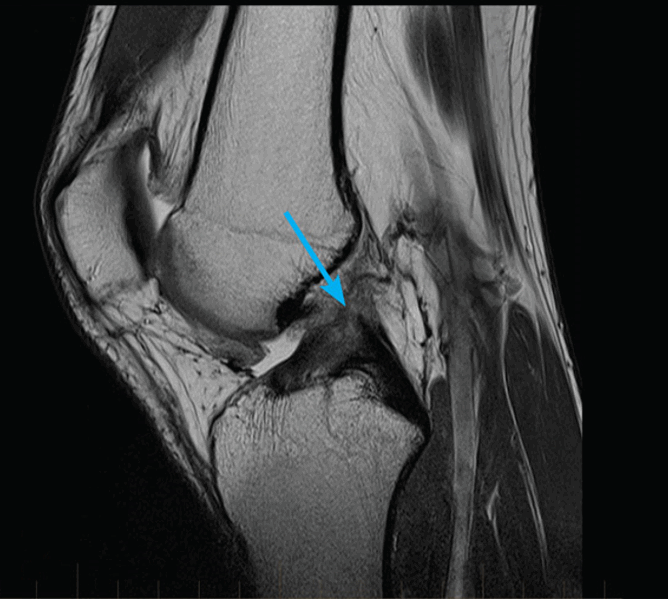

МРТ коленного сустава показывает наличие кисты Бейкера в подколенной ямке (обозначена стрелкой)

Возможно ее обратное развитие вплоть до полного исчезновения, но при условии своевременной диагностики и лечения. При длительном её существовании содержимое кисты затвердевает, формируется спаечный процесс. Возможен ее разрыв, приводящий к появлению острых болей, отеку в подколенной ямке и области голени. В таком случае особое значение приобретает МРТ, которая дает возможность провести дифдиагностику с другими патологиями.

Киста Бейкера

На начальной стадии видна только на МРТ. При прогрессировании может определяться визуально как округлое плотное образование в подколенной области. На этом этапе она уже может вызывать боль при физических нагрузках и дискомфорт при сгибании ноги в колене.